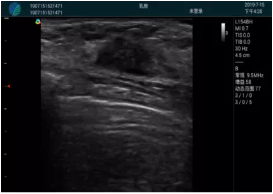

甲狀腺囊性結(jié)節(jié),囊壁鈣化,透聲好

甲狀腺囊性占位